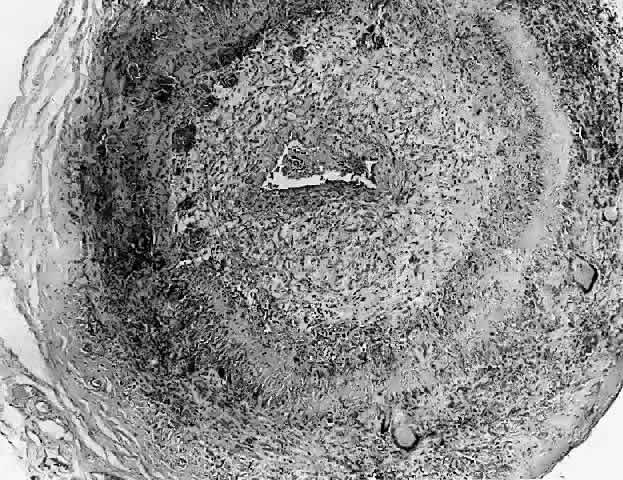

Histopathology

In general, idiopathic orbital inflammation is polymorphic (Figs. 5 AND 6).3,6,7,33,87,88 The cellular response seen in this disease consists of lymphocytes, plasma cells, macrophages, histiocytes, occasional neutrophils and eosinophils, epithelioid cells, and fibroblasts. These are present in varying numbers, depending on the chronicity of the inflammatory process. Intranuclear Dutcher bodies and intracytoplasmic Russell bodies may be present within many of the plasma cells since they actively participate in the inflammatory response. Children tend to have a significant number of eosinophils in their biopsy specimen. Lipogranulomatous inflammation with fat necrosis may also be present. However, the presence of noncaseating granulomas is relatively uncommon.89 This is often associated with foreign body giant cells that are responding to the release of lipid. Perivascular lymphocytic cuffing and capillary proliferation are quite common.3 Occasionally, lymphoid follicles may also be seen.

Fig. 6. Histopathologic sections demonstrating the various pathologic findings associated with idiopathic orbital inflammation. Most commonly these include lymphoid follicles, granulomas, collagen deposition, and a diffuse mixed inflammatory cell infiltrate. The normal tissue architecture is frequently disrupted by these changes. A. Many lymphoid follicles are scattered throughout orbital tissue (H&E, × 63). B. Cells of follicular center are lighter and larger than mantle of mature lymphocytes that surround the germinal zone (H&E, ×160). C. Lacrimal gland elements have undergone atrophy in advanced example of idiopathic dacryoadenitis. Fibrosis and lymphocytes have replaced a considerable amount of gland parenchyma (H&E, ×94). D. Myositis in which lymphocytes are loosely aggregated below center and infiltrate between extraocular muscle fibers (H&E, ×160). E. Cuffing of small vessels by mature lymphocytes. Note loose edematous interstitium between disrupted muscle fibers (H&E, ×240). F. Progressive fibrosis of retrobulbar fat (H&E, ×25).